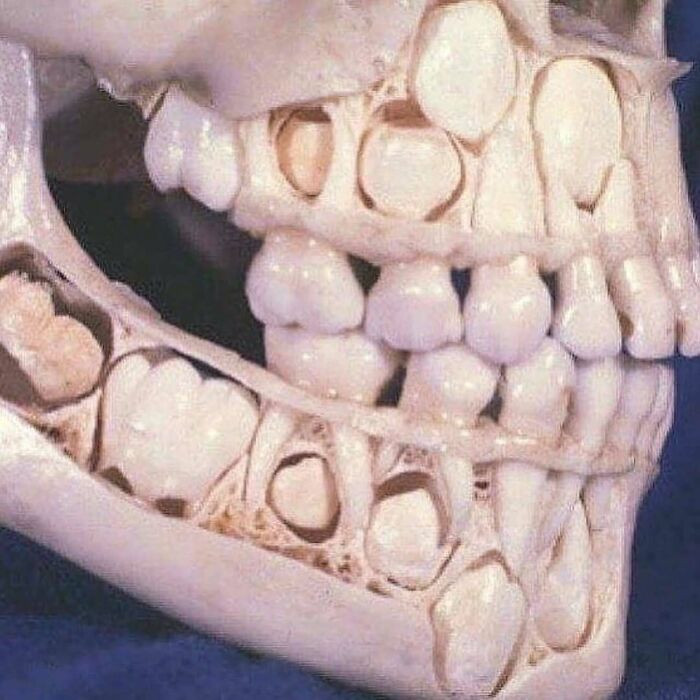

Так выглядит череп ребенка до выпадения молочных зубов